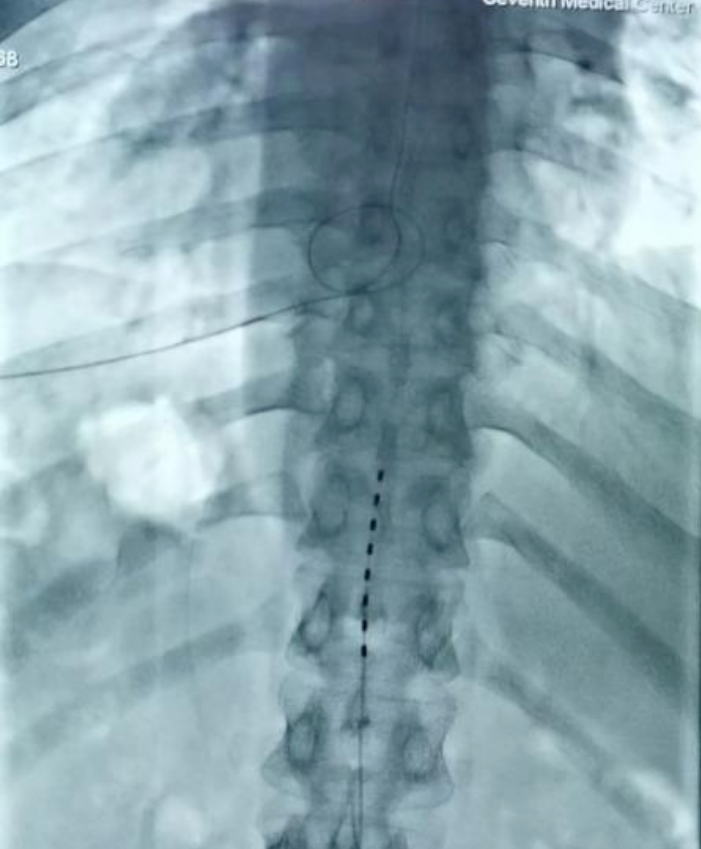

夏主任及其團隊對患者的病情進行了詳細的評估,并與患者及家屬充分溝通后,決定實施脊髓電刺激植入術。在術中電生理和術中影像的引導下,通過穿刺的技術將1根柱狀電極精準放置于T11-T12節段中線位置。